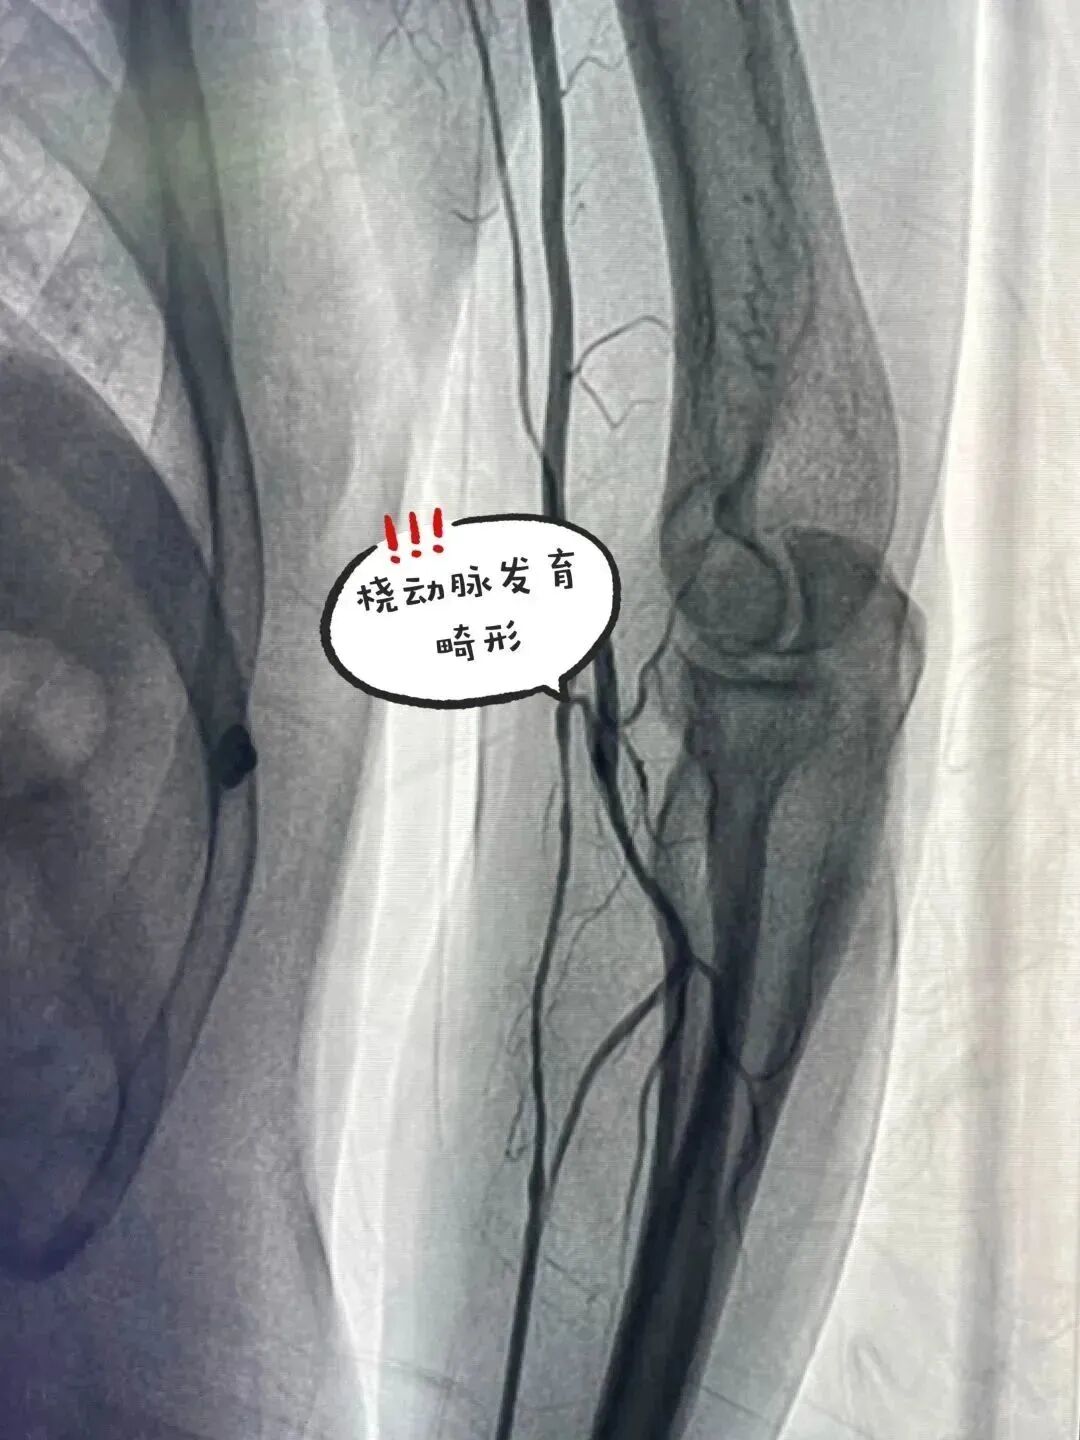

桡动脉血管畸形                                 球囊预扩张闭塞段